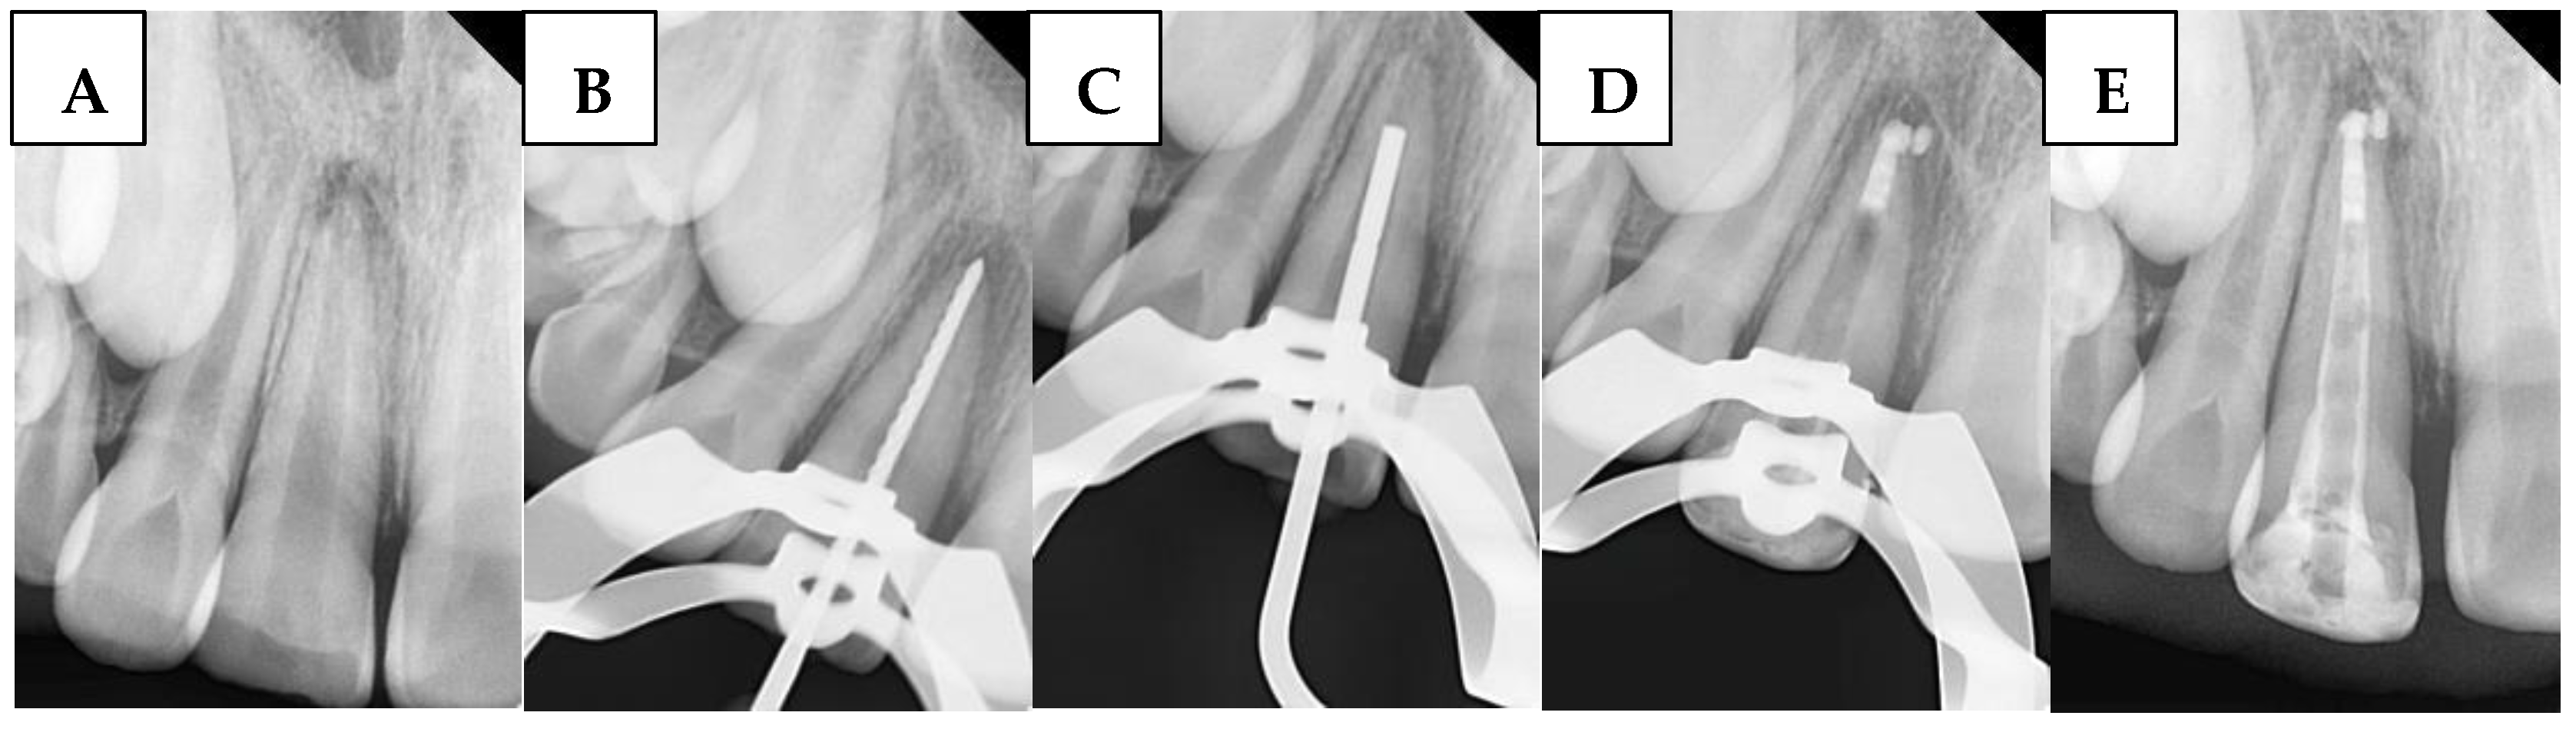

2.6.3. Bioceramic Putty Apical Plugs (BPAP) Group

A radiograph was first taken with the hand plugger to ensure that it reached 4 mm short of the radiographic apex, as specified by the WL. The BioCeramic Putty (BP) (TotalFill® BC RRM™, FKG Dentaire, Le Crêt-du-Locle, Switzerland) was applied to the apical 4 mm of the canal using a modified cannula [34], with placement adapted using a hand plugger and confirmed radiographically. Any BioCeramic extrusion was recorded at this stage in the DPF. The incisors were then temporized with a cotton pellet and glass ionomer filling. The following day, after isolation and removal of the temporary filling and cotton pellet, the remaining canal space was obturated with gutta-percha and BioCeramic Sealer (BS) (TotalFill® BC Sealer™, FKG Dentaire, Le Crêt-du-Locle, Switzerland) using the cold lateral condensation technique. A periapical radiograph confirmed that the canal was obturated without voids or gaps. Figure 2 illustrates the steps of the procedure in the BPAP group.

Figure 2. Sequential steps of the procedure in the BPAP group: (A) Preoperative periapical radiograph, (B) Working length radiograph, (C) Plugger fit, (D) Apical plug formation, and (E) Postoperative radiograph.